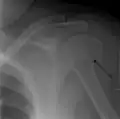

A spiral fracture of the distal one-third of the humerus shaft- A displaced supracondylar fracture in a child